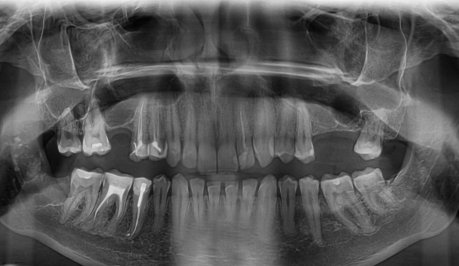

На каких зубах существует вероятность пульпита? 2. Есть ли вероятность, что на снимке присутствуют зубы, такие, что зуб значительно разрушен (от четырёх поверхностей), поэтому здесь требуется восстановление. То есть речь идёт о ситуации кариеса, когда пострадало более трёх поверхностей. Как известно, любой зуб имеет пять поверхностей (1. С внешней стороны. 2. С внутренней стороны (со стороны языка). 3. Со стороны левого соседнего зуба. 4. Со стороны правого соседнего зуба. 5. С жевательной стороны. Я понимаю, что точно диагноз нельзя поставить только по снимку, потому что нужен и визуальный осмотр, но речь идёт просто о возможности (подозрительных зубах и наиболее сложных).

Прям четких пульпитных явлений на снимке я не увидел. Шестой зуб сверху (26), требует установки коронки из-за большого количества пломбы, что по показаниям требуется реставрация вкладкой и коронкой. Не знаю про какой зуб идёт речь, но при разрушении коронковой части зуба более, чем на 50%, необходимо устанавливать коронки. Для более подробной консультации, обратитесь к стоматологу на очный приём.